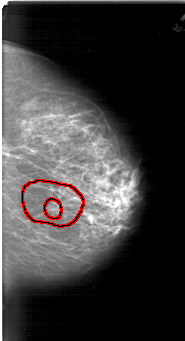

FILE: A_1485_1.RIGHT_CC.OVERLAY

TOTAL_ABNORMALITIES 1

ABNORMALITY 1

LESION_TYPE MASS SHAPE IRREGULAR MARGINS SPICULATED

ASSESSMENT 5

SUBTLETY 2

PATHOLOGY MALIGNANT

TOTAL_OUTLINES 2

BOUNDARY

CORE